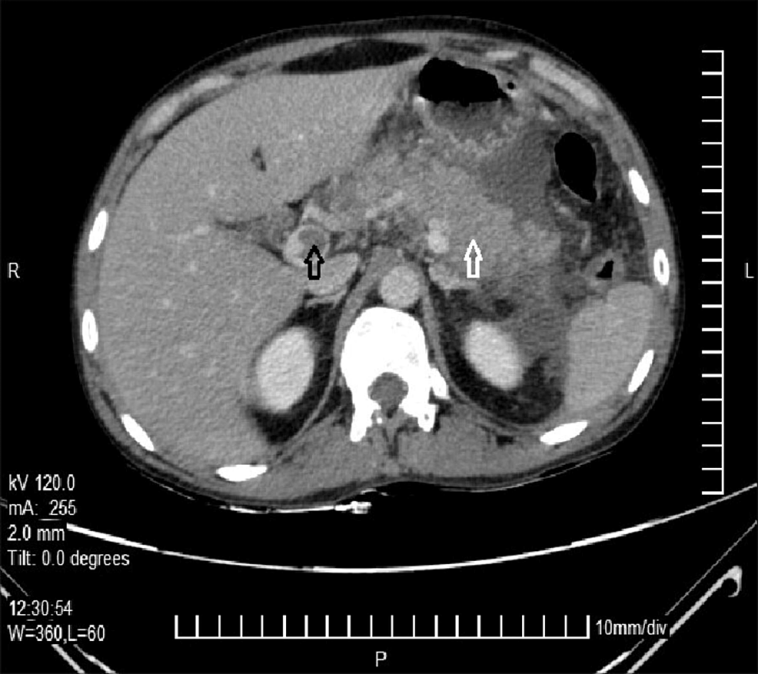

One of the most impressive aspects of modern vascular medicine is the availability of sophisticated imaging techniques. In the specific instance of PVA evolving to EHO, imaging methods such as computed tomography (CT), magnetic resonance imaging (MRI) with gadolinium enhancement, and ultrasonography (US) revealed the fine points of the evolving pathology.

For example, a CT scan initially uncovered the existence of a PVA and measured its dimensions carefully. Later on, an MRI helped reveal both the extension of thrombosis along the portal system and even the formation of collateral blood vessels after the PVA diminished. Ultrasonography provided additional confirmation—with Doppler studies, the absence of blood flow in the main portal vein trunk was noted, while surrounding collateral vessels started exhibiting flow. These imaging techniques offered a roadmap of the patient’s journey, proving invaluable in managing his condition.